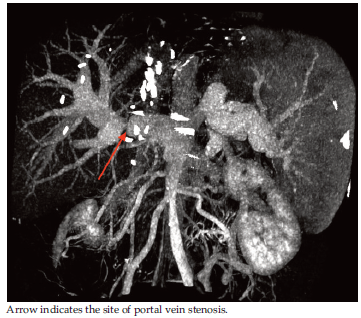

If both criteria were present, then computed tomography (CT) with contrast enhancement was indicated for additional examination and confirmation of the diagnosis of PVS. Thus, all patients underwent contrast-enhanced CT (CECT), and PVS was revealed in all cases (Figure 1).

Figure 1.Three-Dimensional Multidetector Helical Computed Tomography